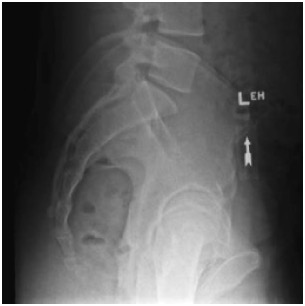

On a MV right lateral image, what bony anatomy can be used to assist with the match

the pubic symphysis and the sacrum

what is the most primary match structure for prostate on lateral imaging?

sacrum is used typically as pubic symphysis is often blurry

if pubic symphysis is sharply defined you an use that